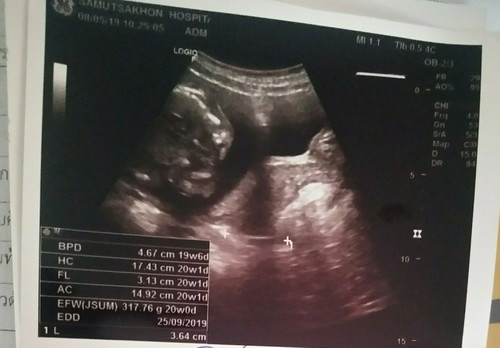

แม่ๆช่วยดูให้หน่อยได้ใหมค่ะว่าน้องเป็นผู้ชายหรือผู้หญิงค่ะ?

มุมดูยากมากค่ะ มองไม่เห็นอวัยวะเพศเลยจ้าาา